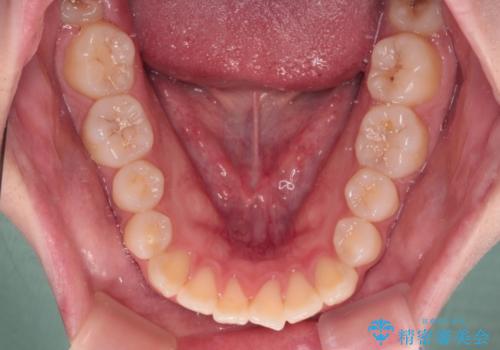

- 前歯が開いて飛び出していることを気にして来院された患者様です。

舌の突出癖により上下前歯は接触できず、更には前方に押し出されて出っ歯になっている状態でした。

上下左右の第一小臼歯4本を抜歯し、ワイヤー装置での抜歯矯正を行っていくのですが、原因である舌の突出癖を改善しないことには治療がうまく進められないため、舌のトレーニングを徹底するよう指導していくこととしました。